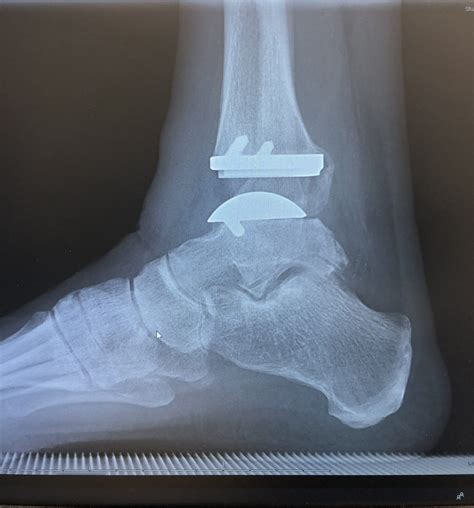

Ankle Replacement - Ankle - Surgery - What We Treat - Physio.co.uk